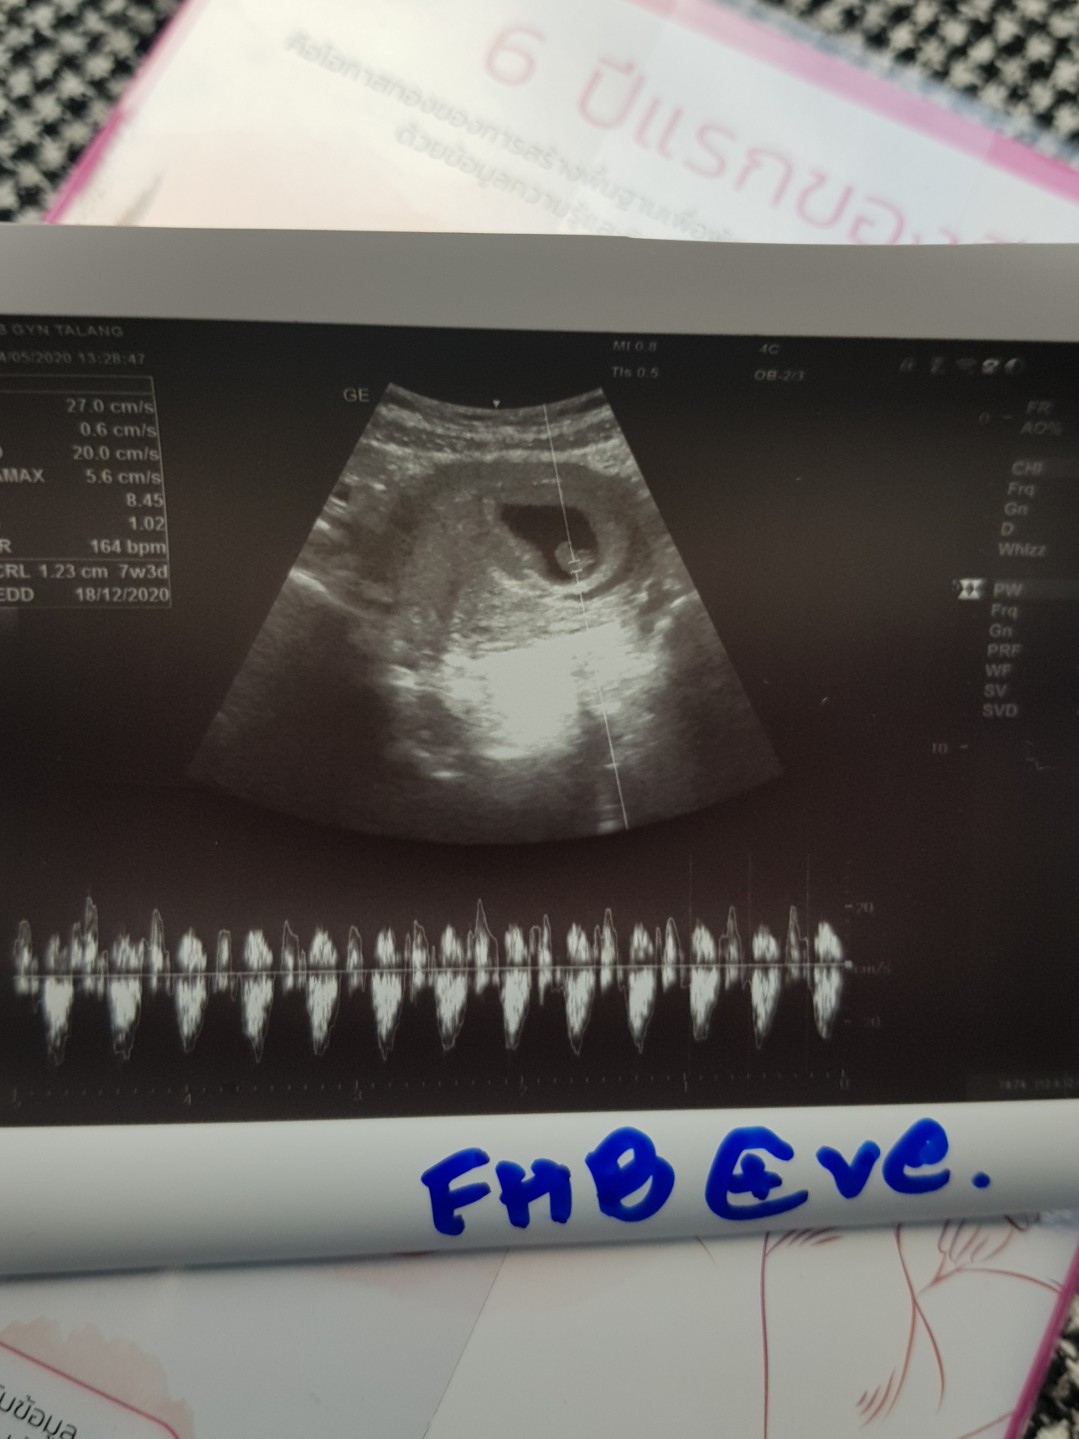

บ้านนี้จ้าาา 18 ธ.ค.😍

แม่น้องคาลิส